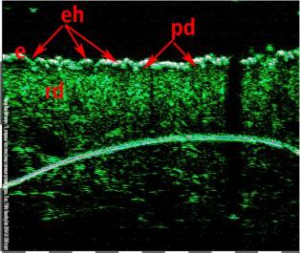

-Μελάνωμα

-Μέτρηση επιπέδων Breslow και Klark σε έμβιο οργανισμό (IN VIVO)

-Διαφοροποίηση τύπων βασικοκυτταρικού καρκινώματος